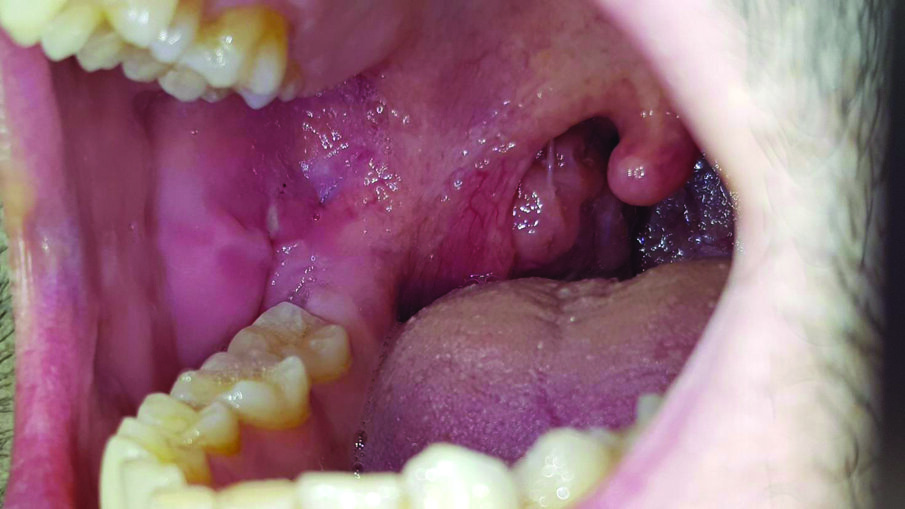

Un paziente di 27 anni sottoposto a una visita di controllo, presenta nel cavo orale a livello della mucosa buccale destra un’afta minor sintomatica, soprattutto quando viene a contatto con il cibo o sostanze liquide. Il paziente ci riferisce che qualche giorno prima di venire alla visita di controllo aveva contratto una sindrome influenzale (Fig. 1). Si prescrive collutorio a base di olio di oliva ozonizzato (Ialozon, Gemavip, Cagliari, Italy) da utilizzare puro come sciacquo orale per 1 minuto ogni 8 ore per 5 giorni e GEL con olio di oliva ozonizzato arricchito con aloe e acido ialuronico (Ialozon gel orale, Gemavip, Cagliari, Italy) 3 volte al giorno per 5 giorni. Dopo 5 giorni la lesione aftosa era completamente regredita (Fig. 2).

Fig. 2 - L’immagine mostra come la lesione sia totalmente regredita dopo 5 giorni di trattamento.